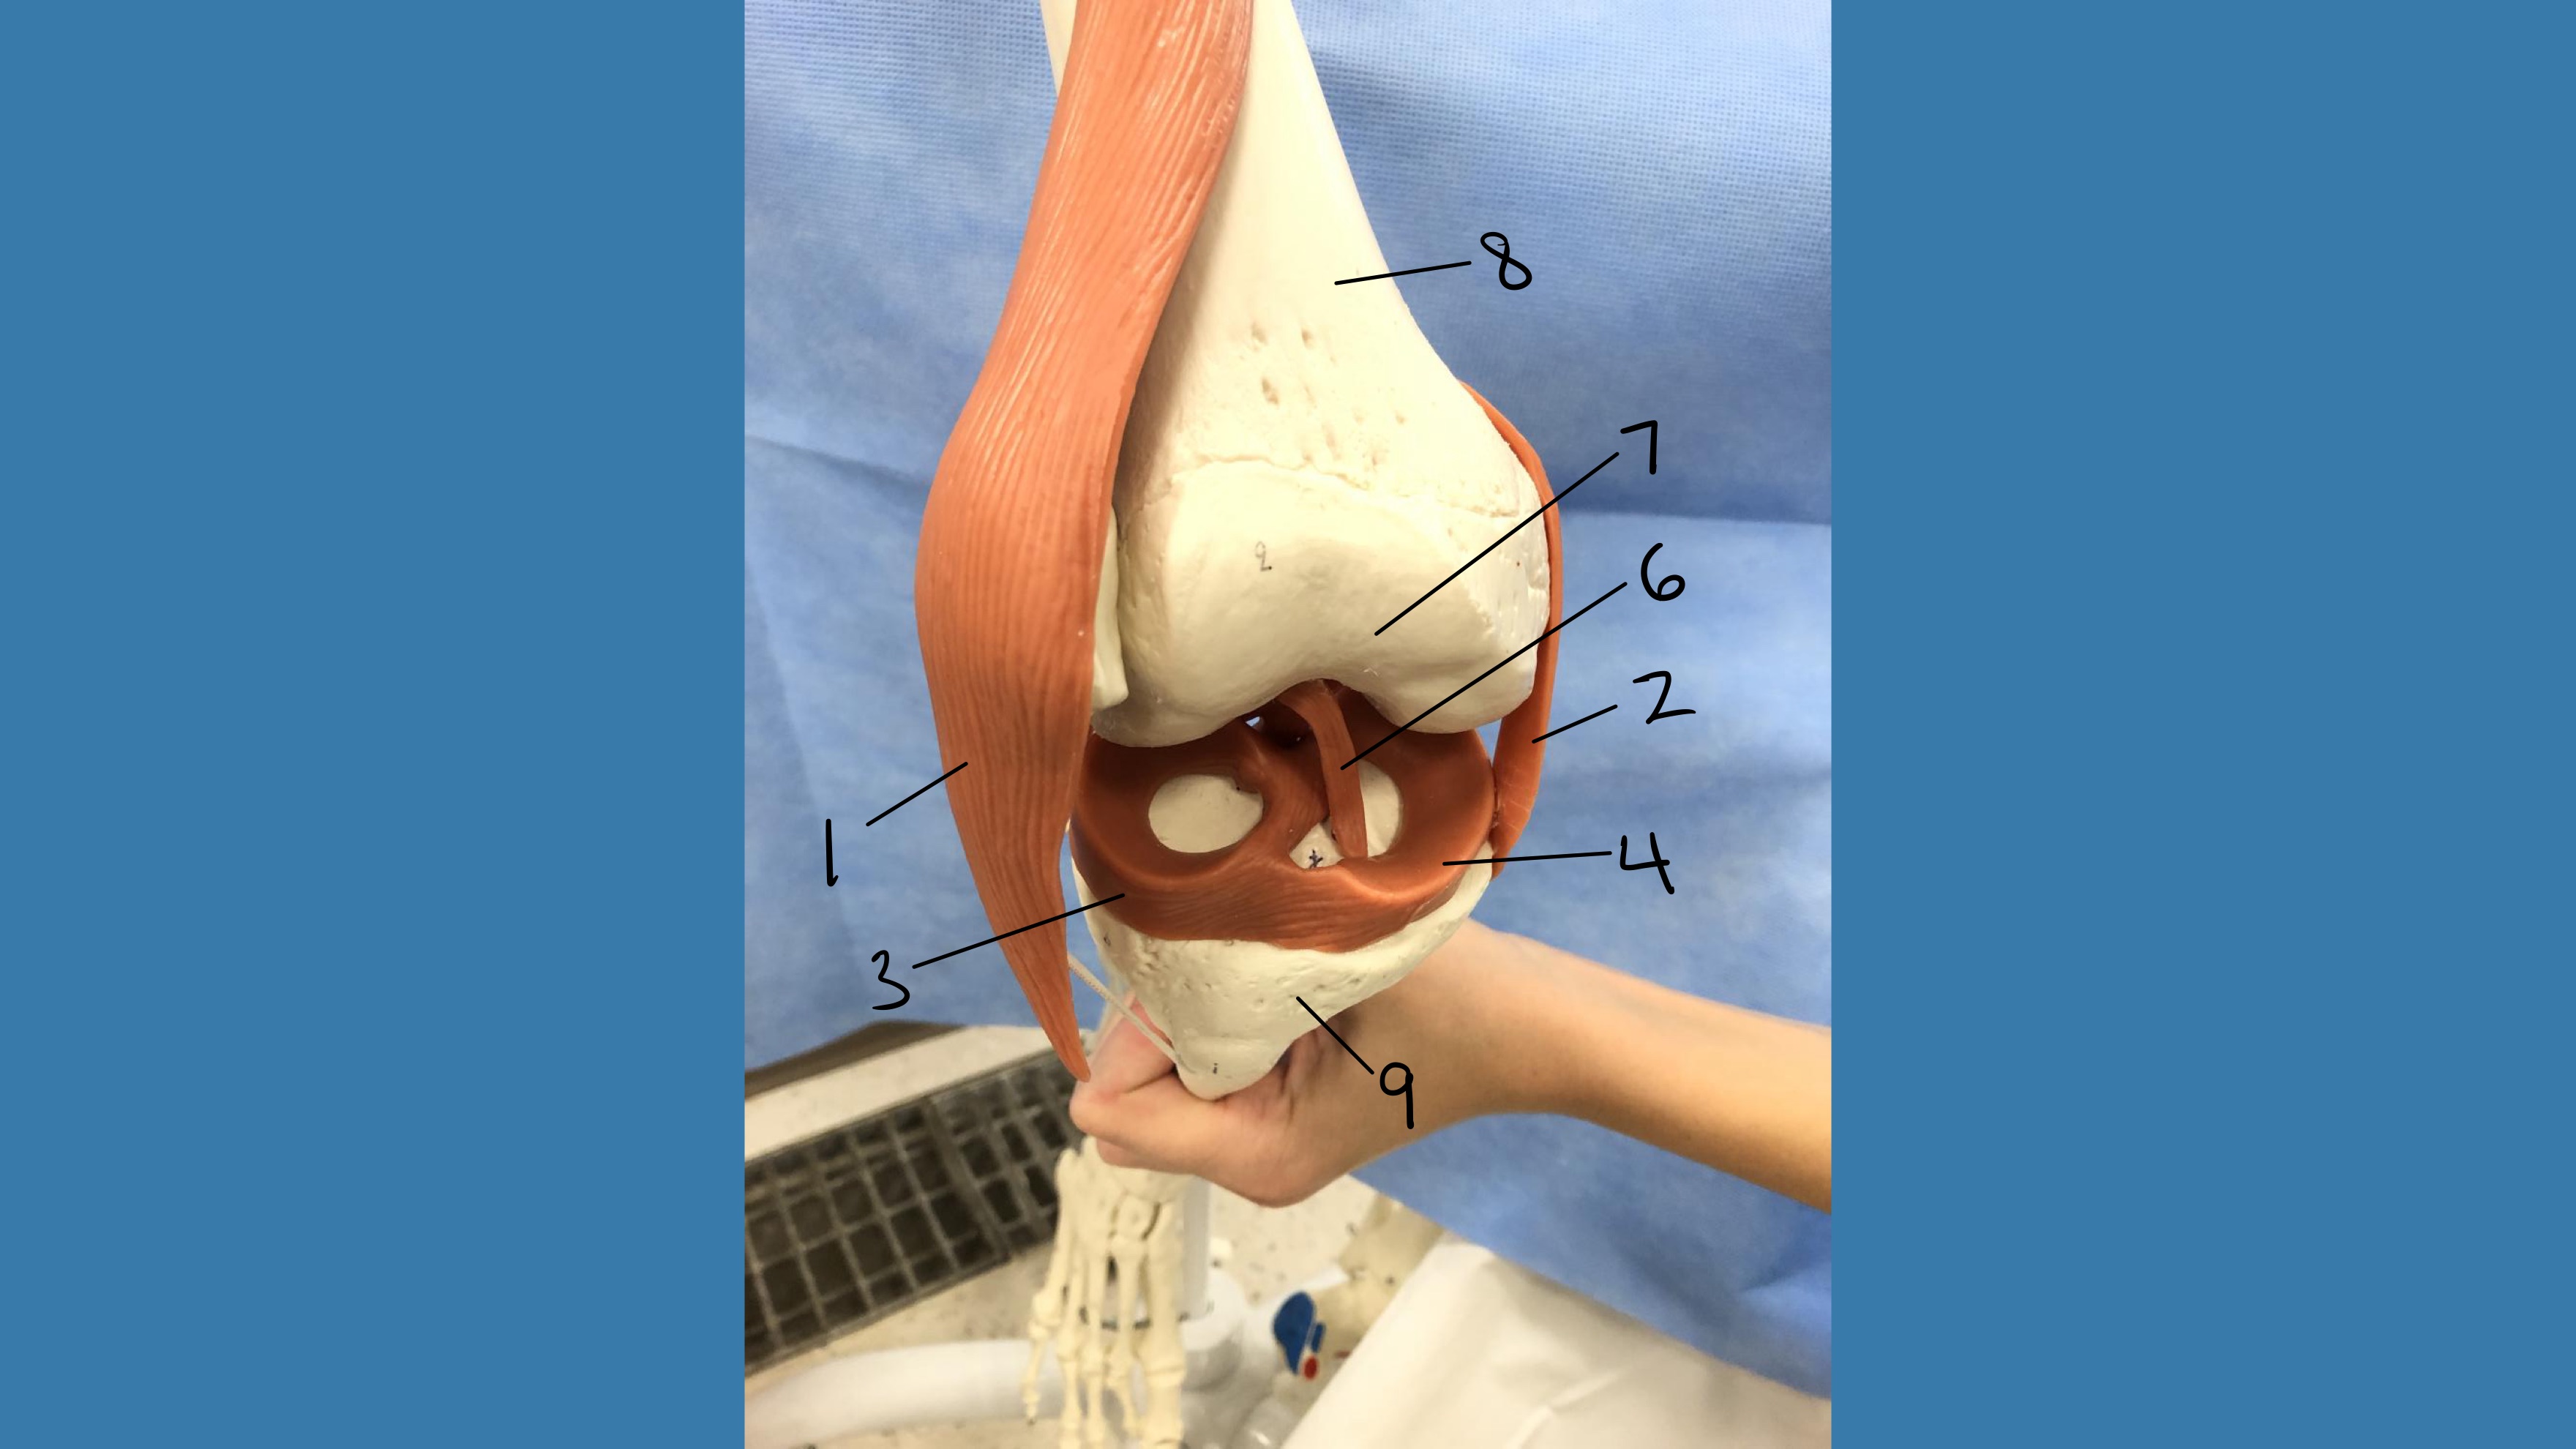

1

lateral collateral ligament

2

medial collateral ligament

3

lateral meniscus

Fibrocartilage

4

medial meniscus

6

anterior cruciate ligament

7

articular cartilage

hyaline cartilage

8

femur

9

tibia